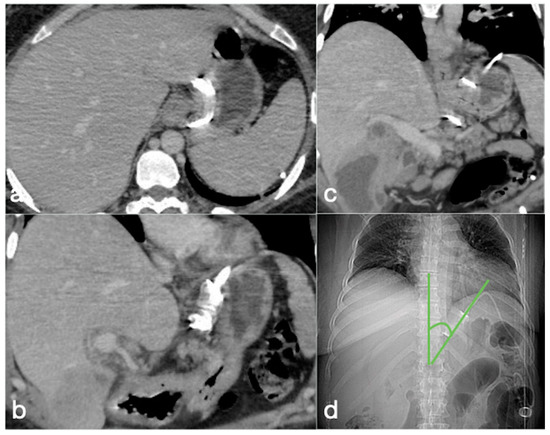

Figure 2. Correct positioning of the gastric banding seen in the CT axial (a) and coronal (b,c) views. (d) The CT localizer at the phi angle. This is the angle that needs to be reviewed to confirm that the gastric band is normally positioned. This is formed by the profile of the gastric band and the vertical axis of the spine on frontal view. The normal range is between 4° and 58°. In the shown case, it is at 40°.

AGB consists of a silicone band with an inflatable balloon cuff placed around the proximal stomach, approximately 2 cm distal to the gastro-esophageal junction, creating a small gastric pouch in communication with the remnant stomach (Figure 2). The anterior gastric wall can be sutured over the band to the gastric pouch to decrease the chances of band slippage. The band is then tubing-connected to a port placed subcutaneously in the abdomen. Through percutaneous aspiration or injection of saline or radio-opaque contrast into the port, the size of the balloon inside the band can be decreased or increased, thereby adjusting the stomal width [12].

On an AP radiograph, the superior angle between the longitudinal axis of the gastric band and the spinal column (φ angle, phi) should be from 4 to 58 degrees, and the correct spatial position of the gastric band is approximately 5 cm below the left hemidiaphragm. The distal displacement of the band, with an increased distance between the band and the left hemidiaphragm [28] and a change in band orientation (with rotation along the horizontal axis and loss of overlapping between the anterior and posterior portions of band that results in “O” shape visible on AP projection [4]) is associated with value alterations of the superior angle composed of the longitudinal axis of the gastric band and the spinal column (φ angle), as measured by AP projection (Figure 2 and Figure 10) [28].